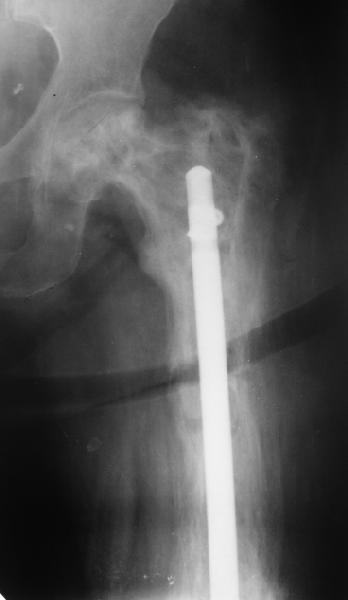

Еще один пример. Пациентка с юга России, прислала рентгенограммы через год. На сегодня прошло 2 г. 8 мес. после операции. Несмотря на не очень убедительный процесс сращения, пациентка ходит. Учитывая остеопороз при Педжете, решили, что динамизировать вообще не нужно.